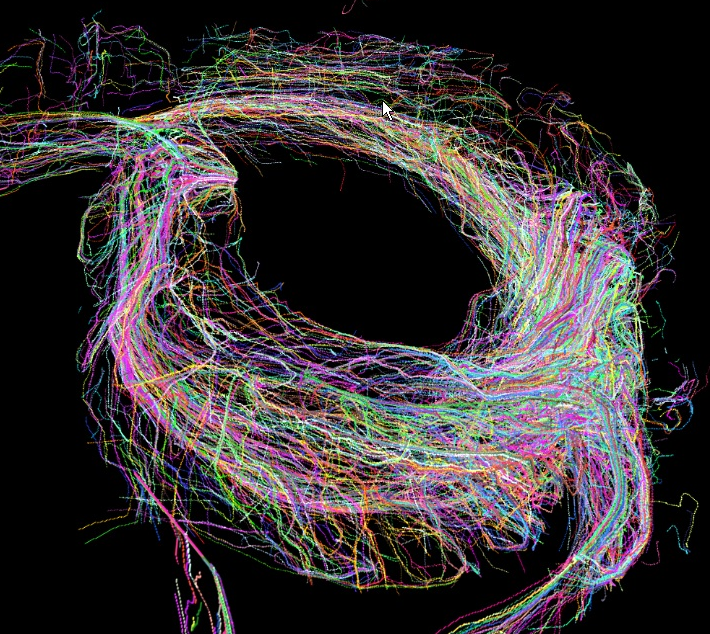

重症心不全における心筋配向変化が心機能増悪をもたらす機序の解明

(科学研究費基盤B)

重症心不全における心筋配向の変化と乱れが心収縮能と拡張能・心臓リモデリングに及ぼす影響をMicro CTと心機能シミュレーション技術を用いて解析し、心不全悪化のメカニズムを力学的観点から明らかにすること

心不全が進行した心臓では、心形状が円錐形から球状化し、心筋配向がらせん構造から水平方向に傾き、さらに収縮効率が悪化する(図1)。さらに心筋シート(右図)の傾きは心室壁伸展に伴い、垂直方向に傾く。

MicroCTを用いて正常心と不全心の心筋配向変化、心筋シートの傾きを評価する(名古屋大学工学部森健策教授研究室)。UT-Heart研究所の心臓シミュレーション技術に上記結果を組み込み、心機能(収縮能&拡張能)に与える影響を検討する。

| 図9 microCT画像 | 図10.心筋配向ベクトル表示 |